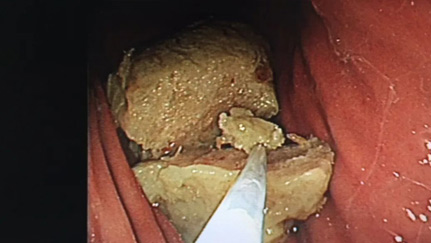

那么作为内镜科水管工,水管有“石头”可不行。

【健康科普】健康提醒!秋冬季,这种水果不能贪多,小心“胃石”找上你(图2)

上图“石头”已经将近两周了

【健康科普】健康提醒!秋冬季,这种水果不能贪多,小心“胃石”找上你(图3)

已经合并了常见的并发症,多发浅溃疡形成

并且,“石头”表面有层“厚厚的壳”

利用平时工作最常用到的圈套器,也可以用来切割胃石,而且减轻患者经济负担

“石头壳”很硬,用活检钳慢慢夹碎出一条缝隙

目的是内部可以接触到碳酸氢钠溶液,并且,给下一步出场的圈套器留下一个切割位置